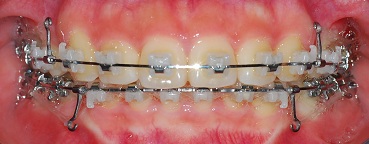

<정면사진>

측면에서 보면 아직 입이 조금 나와잇져! 근데 정말 많이 들어갓어요ㅎㅎ